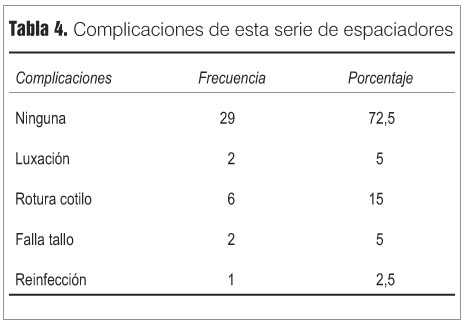

Las complicaciones de toda la serie de espaciadores se muestra en la tabla 4, y, como se ve, las mismas son muy poco frecuentes. Cuatro de los casos requirieron el segundo tiempo por alguna complicación.

Veintisiete pacientes permanecen con el espaciador al momento del último control, con un seguimiento promedio de 48 meses (entre 12 y 96 meses), con una evaluación clínica excelente y buena en la mayoría de los casos y con excelente resultado radiológico (figura 3). Debe destacarse que ninguno de estos pacientes acepta la realización del segundo tiempo en este momento, lo que habla de la conformidad con la situación actual, y que, además, los peores resultados clínicos se asociaron a pacientes con múltiples patologías médicas concomitantes, a edad mayor de 75 años, o a alguna complicación del espaciador.